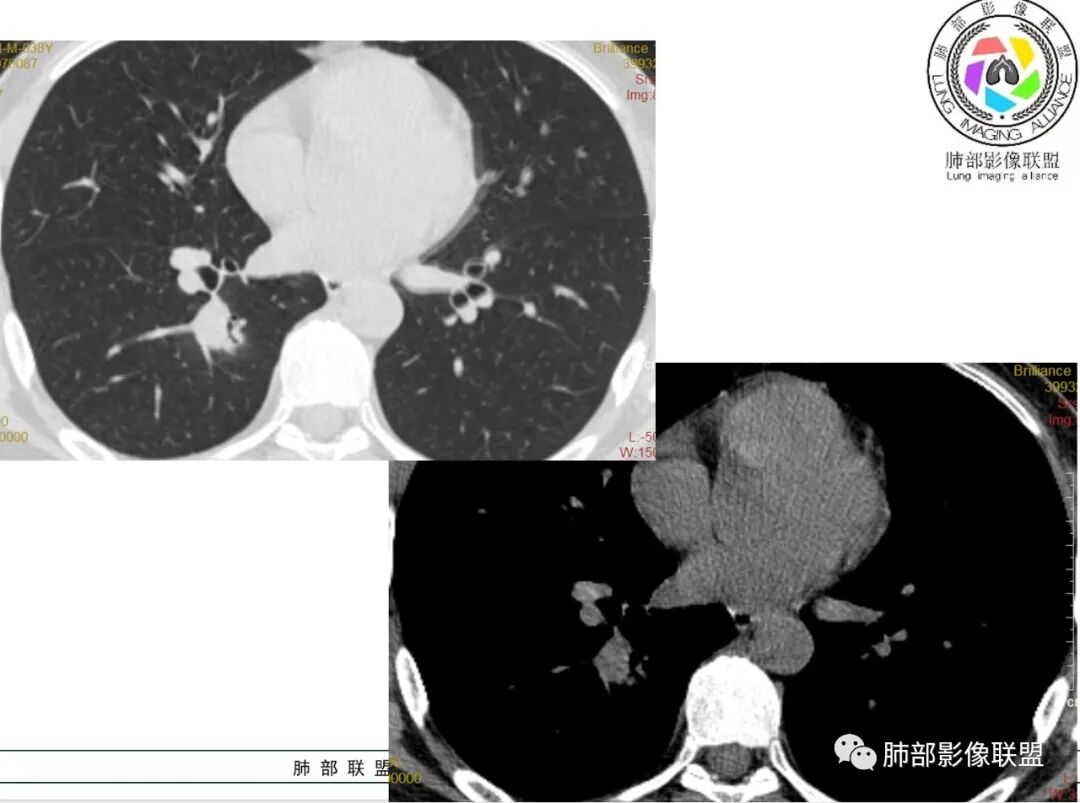

尘缘:中年男性,咳嗽咳痰伴乏力多汗,无发热,偶有畏寒。期间至某中医院治疗服中药后,症状好转。白细胞与血沉稍高。影像表现:左上肺团块状影(增强后CT值约22,伴有血管漂浮),中间支气管明显扩张,伴有小空洞形成,周围有晕,右下肺多发团块状影(增强后CT值约48),无明显支扩,伴胸膜下多发小结节,13天后复查,左上肺主病灶无明显变化,其他病灶范围有缩小,空洞消失,右下肺病灶变化不明显。

* 差不多2周,有差异吗?半个月左右吸收明显,肿瘤不考虑,炎性没问题。

* 看看这边缘,平直、凹陷,炎性没问题,修复阶段。提示亚急性,有OP形成;多发,斑片,强化偏轻,常规抗炎效果不佳。首先:诊断炎性病变,三亚,多发病灶,斑块状,周围GGO,类鼻疽要考虑。

2、影像资料:双肺多发的小结节、斑片状及不规则型的实性病灶,周围有晕,沿支气管血管束分布,部分的病灶周围可见磨玻璃样影、支气管的扩张以及小的空洞。增强扫描病灶,轻度强化内部见支气管造影征。部分的病灶,支气管有扩张,内壁凹凸不平的改变,纵隔淋巴结未见肿大。病灶整体的形态还是多样化,部分位于胸膜下。

3、治疗:经氟康唑治疗2周后,影像上以边缘的磨玻璃样病灶的吸收为主。